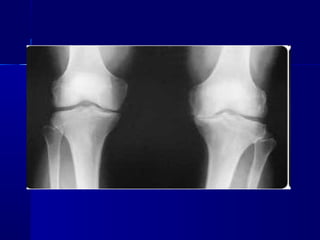

   Total knee replacement (TKR)

and hip fracture coming for

replacement are the two most

common surgical procedures

• 5.

Total knee replacement (TKR) and hip fracture coming for replacement are the two most common surgical procedures after the sixth decade of life.

• 6.

Most of the patients have degenerative joint disease, commonly osteoarthritis (OA).

• 7.

Other conditions requiring knee or hip replacement are injury to the neck of femur or knee joint, knee deformity, rheumatoid arthritis and gout.